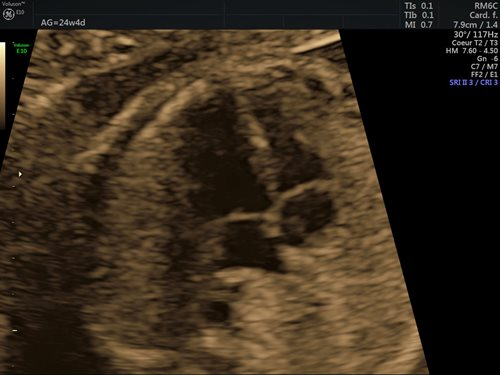

Dans la grande majorité des cas (90 %), l’étiologie des cardiopathies congénitales est multifactorielle, un facteur de risque classique comme des antécédents familiaux au 1er et 2e degré, la présence d’une anomalie chromosomique, d’un diabète maternel de type 1, d’une phénylcétonurie, la prise de certains médicaments ou une infection n’étant pas retrouvé. Pour cette raison, un dépistage systématique par échocardiographie foetale reste indispensable, idéalement entre 18 et 22 semaines de gestation. Le dépistage recommandé consiste en l’obtention d’une vue des 4 cavités cardiaques (fig. 1) et d’une vue des voies d’éjection (fig. 2). (2)

Figures 2